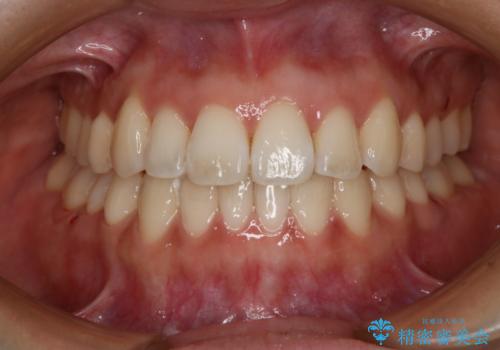

【審美装置】前歯で噛めない!抜歯しないで治したい

MARPEで非抜歯矯正|オープンバイトと八重歯を改善